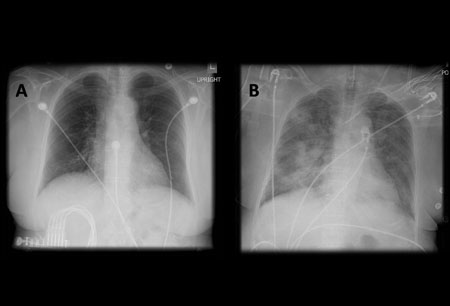

Acute aspiration

A. Portable upright chest x-ray before aspiration; B. Chest x-ray 1 hour after aspiration, showing bilateral diffuse alveolar infiltrates, worse at the bases on the right side

From the collection of Dr Henri Colt